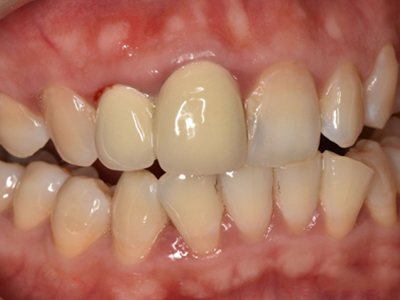

慢性龈炎又称边缘性龈炎或单纯性龈炎,主要表现为游离龈和龈乳头因炎性水肿,而变为鲜红或暗红色,龈缘变厚,龈乳头圆钝肥大。慢性龈炎的患病率高,治愈后仍可复发,部分患者可发展成为牙周炎。

慢性龈炎的病损部位一般局限于游离龈和龈乳头,以前牙区为主,尤其以下前牙区最为显著,患者常因刷牙或咬硬物时牙龈出血而就诊。游离龈和龈乳头颜色变为鲜红或暗红色,病变较重时炎性充血可波及附着龈。龈缘变厚,龈乳头圆钝肥大,可增生呈球状,覆盖牙面。牙龈松软脆弱,缺乏弹性。

当牙龈以增生性反应为主时,龈缘和龈乳头呈坚韧的实质性肥大,质地较硬而有弹性。龈沟液量增多,还可能出现龈沟溢脓现象。